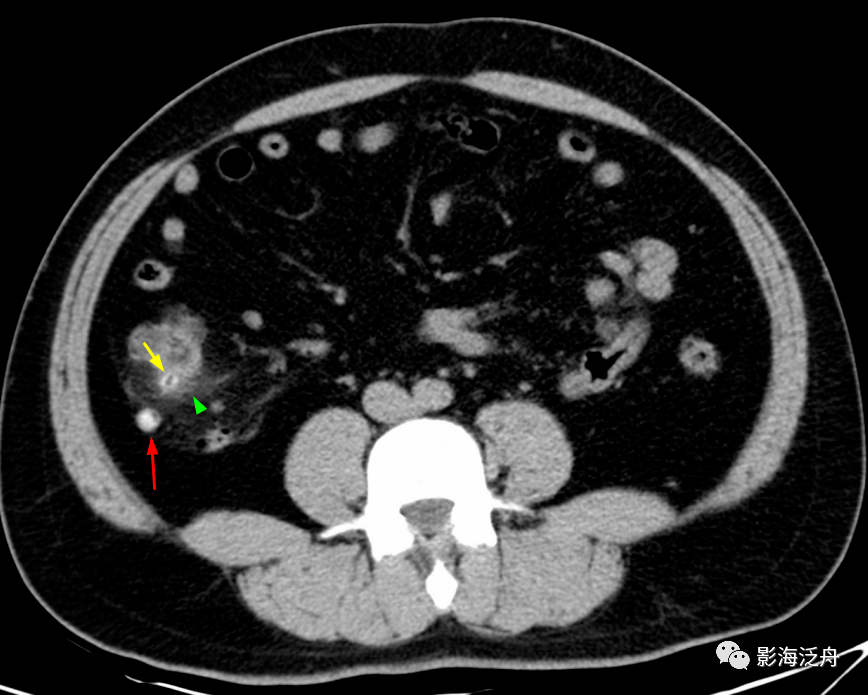

壁厚而强化,近端管腔内见高密度粪石影,注意渗出(绿箭头)以阑尾根部为

红色箭头所指为阑尾根部,可见明显粪石梗阻,黄色箭头所指为阑尾体部